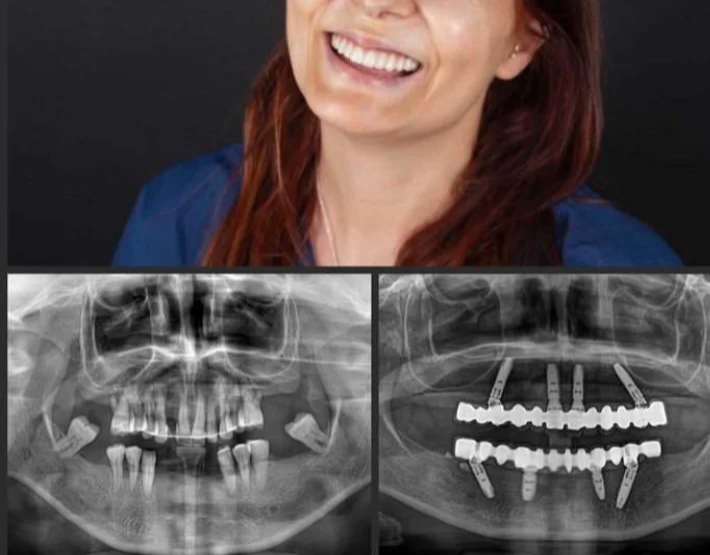

All on 4 Full Arch Implant Toronto. After upper and lower All on Four Implants, functionality, aesthetics, lip and cheek support and lower face height regained

All on 4 Full Arch Implant Toronto. Close-up picture of All on Four implant fixed bridges

Before upper and lower All on Four implants

Loss of multiple teeth causes loss of lip and cheek support and reduced lower face height